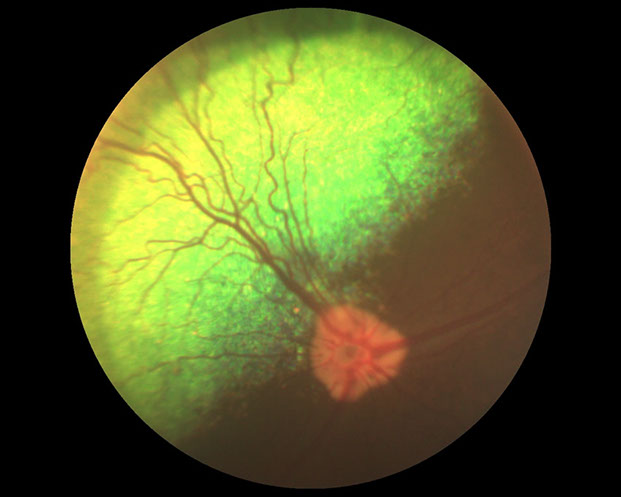

DOENÇA RETINIANA: COLOBOMA DE NERVO ÓPTICO